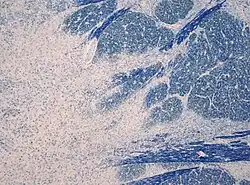

A mielinólise pontina central é uma condição neurológica que envolve danos graves à bainha de mielina das células nervosas na ponte (uma área do tronco cerebral). Ela é predominantemente iatrogênica (induzida por tratamento) e é caracterizada por paralisia aguda, disfagia (dificuldade para engolir), disartria (dificuldade para falar) e outros sintomas neurológicos.

A mielinólise pontina central foi descrita pela primeira vez como um distúrbio em 1959. O artigo original descrevia quatro casos com desfechos fatais e os achados na autópsia. A doença foi descrita como uma doença relacionada ao alcoolismo e desnutrição.[1] "Pontina central" indicava o local da lesão e "mielinólise" era usada para enfatizar que a mielina estava afetada. Os autores evitaram intencionalmente o termo "desmielinização" para descrever a condição, a fim de diferenciá-la da esclerose múltipla e de outros distúrbios neuroinflamatórios.[2]

A teoria atualmente aceita afirma que as células cerebrais ajustam suas osmolaridades alterando os níveis de determinados osmólitos, como inositol, betaína e glutamina, em resposta à variação da osmolalidade sérica. No contexto do baixo nível crônico de sódio plasmático (hiponatremia), o cérebro compensa diminuindo os níveis desses osmólitos dentro das células, para que elas possam permanecer relativamente isotônicas em relação ao ambiente e não absorver muito líquido. O inverso é verdadeiro na hipernatremia, na qual as células aumentam seus osmólitos intracelulares para não perder muito fluido para o espaço extracelular.[26]

Com a correção da hiponatremia com fluidos intravenosos, a tonicidade extracelular aumenta, seguida por um aumento na tonicidade intracelular. Quando a correção é muito rápida, não há tempo suficiente para que as células cerebrais se ajustem à nova tonicidade, ou seja, aumentando os osmoles intracelulares mencionados anteriormente. Se os níveis de sódio sérico subirem muito rapidamente, o aumento da tonicidade extracelular continuará a expulsar a água das células do cérebro. Isso pode levar à disfunção celular e à mielinólise pontina central.[27][28]